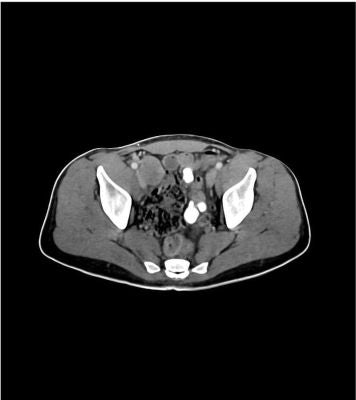

This phantom simulates a contrast medium-enhanced abdomen and pelvis in portal venous phase. It covers the first lumbar vertebra to the perineum. It has iliac lymph node masses on the right side.

The phantom can be used in CT (including CBCT) to evaluate and optimize imaging performance and post-processing applications, including AI-enabled applications. It is also suited for training purposes. The phantom provides a detailed and realistic simulation of soft and bone tissue. Air voids are filled with a cellulose-polymer composite of approx. -160 HU.